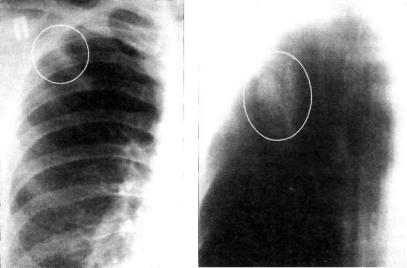

Иллюстрации по теме очагового и инфильтративного туберкулеза

Раздел: Фотодневник открытий